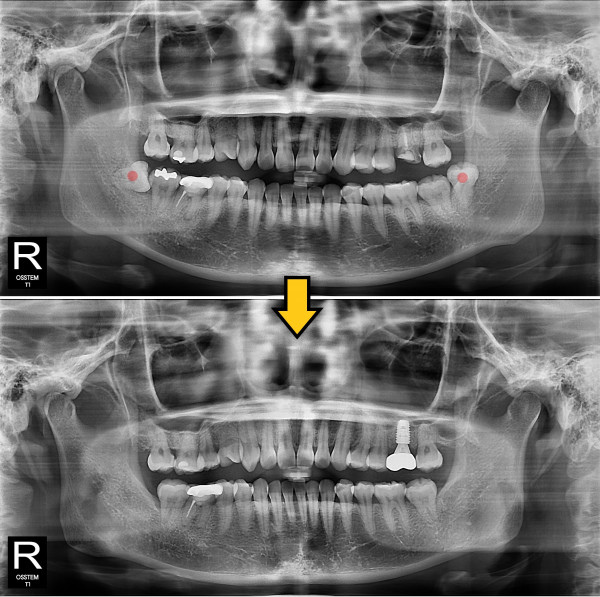

사랑니발치 20대/여성

ae27575af29d49719312fde5a1f0cca6_1764402427_3314.jpg

5e20e086184bc11a2d853605b7813944_1764319752_9378.jpg